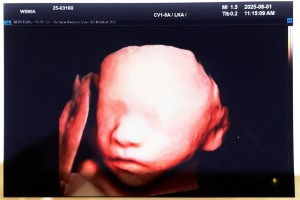

둥둥이를키우자

2025-08-01

둥둥이~오늘 얼굴 보여줘서 고마워!

입체초음파에서 네 얼굴을 보고싶았는데 은근 안보여주는 아기들도 있다고 하더라구! 첨에 딱 보기 시작했을때 얼굴 앞에 손을 두고 있어서 아 오늘 얼굴 못보는 건가? 했는데 어느새 손을 내리고 너무 예쁘게 잘 보여주고 있더라구!!! ㅎㅎㅎ엄마는 열심히 포인트 모아서 네 얼굴을 꼭 볼거야! 고마워 김둥둥~~